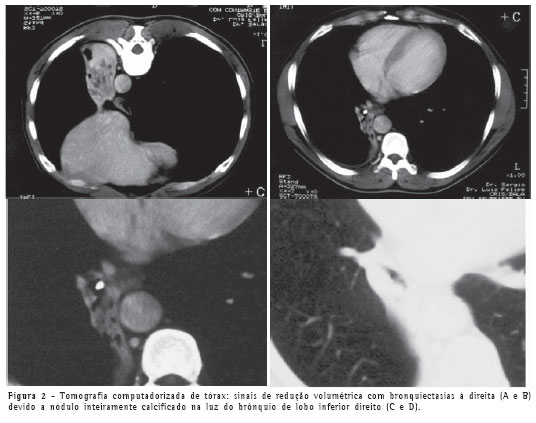

As radiografias do tórax nas incidências póstero-anterior e perfil evidenciaram sinais de redução volumétrica do lobo inferior direito, com borramento do contorno cardíaco desse lado (Figura 1).

A tomografia computadorizada de tórax confirmou a atelectasia e mostrou pequena lesão calcificada em luz de brônquio no lobo inferior direito (Figura 2), além de bronquiectasias com provável impactação mucóide no lobo pulmonar colapsado.